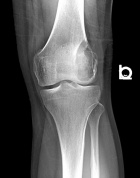

Patient is a 20 y/o male with a history of L. knee GCT s/p excision 11 months ago.

He presents w/ increasing L. knee pain; PMH: GCT; PE L. knee with no effusion + tenderness to palpation over lat. fem. condyle; + tenderness w/ PROM 0-95